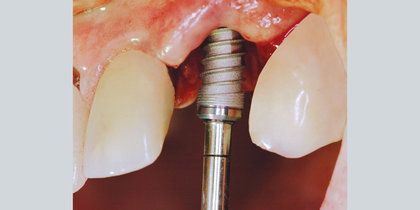

Glidewell HT Implant Macro Shot

Proven, Time-tested Implant Design Features

Designed with purpose

Tapered body

Tapered body for use in anatomically constricted areas